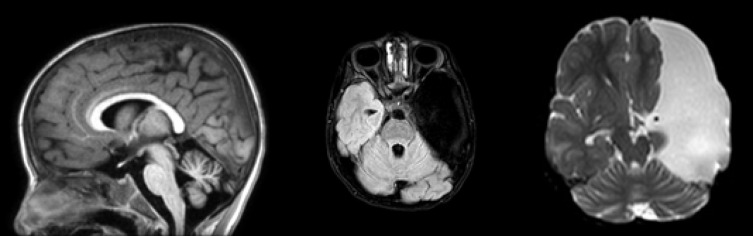

Ataxiatelangiectasia (A-T) is an infrequent genetic neurodegenerative disorder inherited autosomal recessively. It is mainly characterized by early-onset progressive cerebellar ataxia and dilated capillaries in the oculocutaneous regions especially conjunctivae so-called telangiectasia. A-T is a multisystem disorder and requires multi-disciplinary approach to management. Diagnosis is difficult in some cases because presentation is not in the same manner and showing a phenotypic spectrum. In atypical cases serum immunoglobulins and alfa fetoprotein are normal and telangiectasia is absent. We present a 5.5-year-old boy with progressive cerebellar ataxia and history of repeated sino-pulmonary infections that was homozygote for ataxia-telangiectasia mutated gene and had a giant arachnoid cyst in left hemisphere. It is important to keep in mind those cases with ataxia and repeated sino-pulmonary infections may be ataxia telangectasia patients. Genetic study is helpful and confirms the diagnosis by showing ataxia-telangiectasia mutated gene.